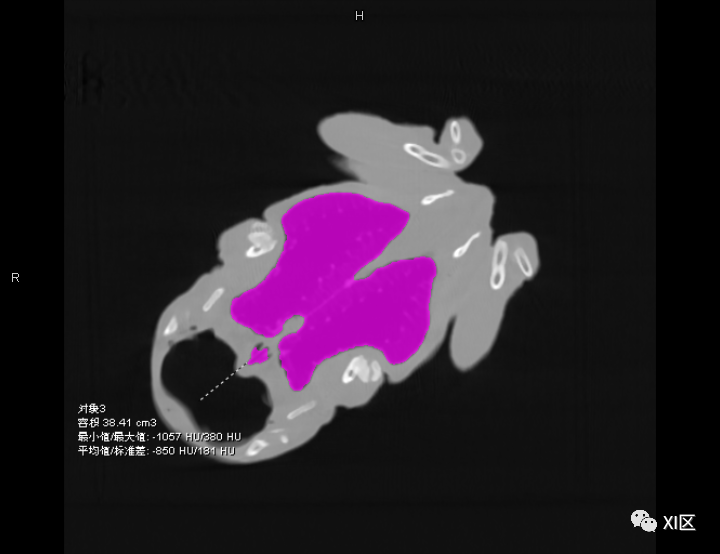

牛蛙三维重建,肺几乎占了整个胸腹腔

首先,

我们看一下牛蛙的肺

这只牛蛙的肺体积非常大

测量发现

体积为38.41ml

之前我们知道了这只牛蛙的总体积

简单计算后发现

牛蛙的肺占全身体积的

13.14%

牛蛙志愿者的肺部CT为38.41ml

作为对比,正常体型的成年人

平静状态下

肺部体积约为全身体积的4%左右

可以说

牛蛙的肺比人大3倍以上